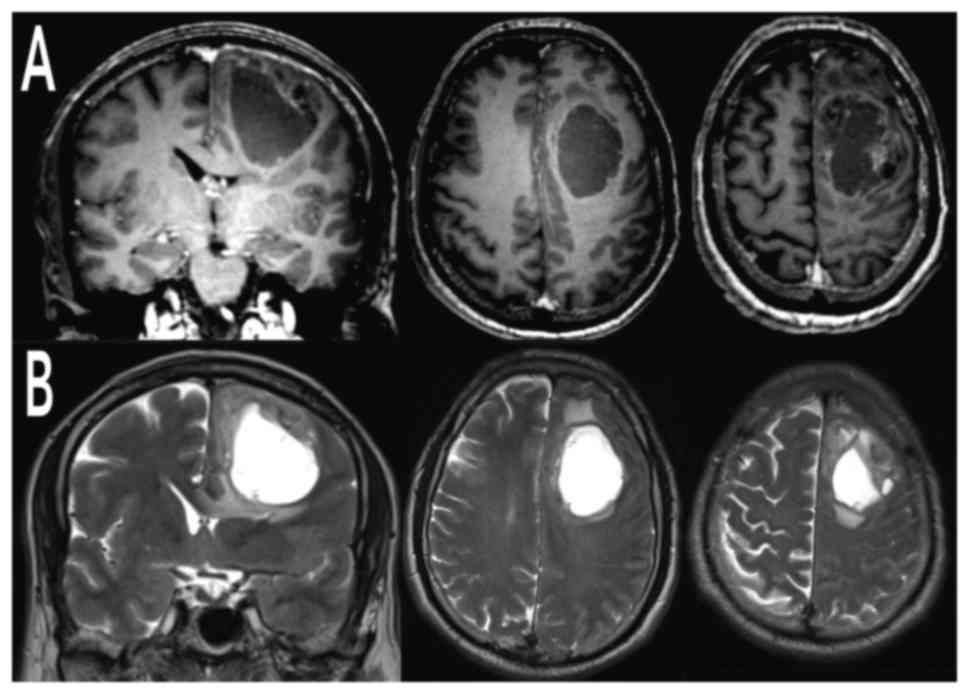

On admission, neurologic examination evidenced a mild right downward drop to the antigravitary Mingazzini test, a flattening of the nasolabial fold and a slight ideomotor slowdown with Karnofsky Performance Status (KPS) 100%. No speech disorders were detected. Computed tomography (CT) scan of the head and contrast-enhanced MRI of the brain uncovered a voluminous left frontal cystic lesion (AP 54 mm × LL 37 mm) with compressive effect and perilesional edema. The lesion presented heterogeneous post-contrastografic enhancement of the cystic walls and multinodular component anchored to the anterosuperior portion of the cyst lesion (Fig. 1). Total body (TB) CT scan did not show any extracranial localization.

Figure 1.

Preoperative brain MRI. Preoperative (A) contrast-enhanced and (B) T2-weighted, coronal and axial MRI cuts showing a large left frontal cystic lesion presenting a heterogeneously contrast-enhanced tissutal component and mild perilesional edema. MRI, magnetic resonance imaging.